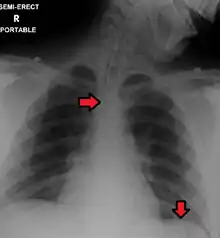

An endotracheal tube and nasogastric tube as seen on CXR. Both in good position.

Great care must be taken to ensure that the tube has not passed through the larynx into the trachea and down into the bronchi. The reliable method is to aspirate some fluid from the tube with a syringe. This fluid is then tested with pH paper (note not litmus paper) to determine the acidity of the fluid. If the pH is 4 or below then the tube is in the correct position. If this is not possible then correct verification of tube position is obtained with an X-ray of the chest/abdomen. This is the most reliable means of ensuring proper placement of an NG tube.[8] The use of a chest x-ray to confirm position is the expected standard in the UK, with Dr/ physician review and confirmation. Future techniques may include measuring the concentration of enzymes such as trypsin, pepsin, and bilirubin to confirm the correct placement of the NG tube. As enzyme testing becomes more practical, allowing measurements to be taken quickly and cheaply at the bedside, this technique may be used in combination with pH testing as an effective, less harmful replacement of X-ray confirmation.[9] If the tube is to remain in place then a tube position check is recommended before each feed and at least once per day.